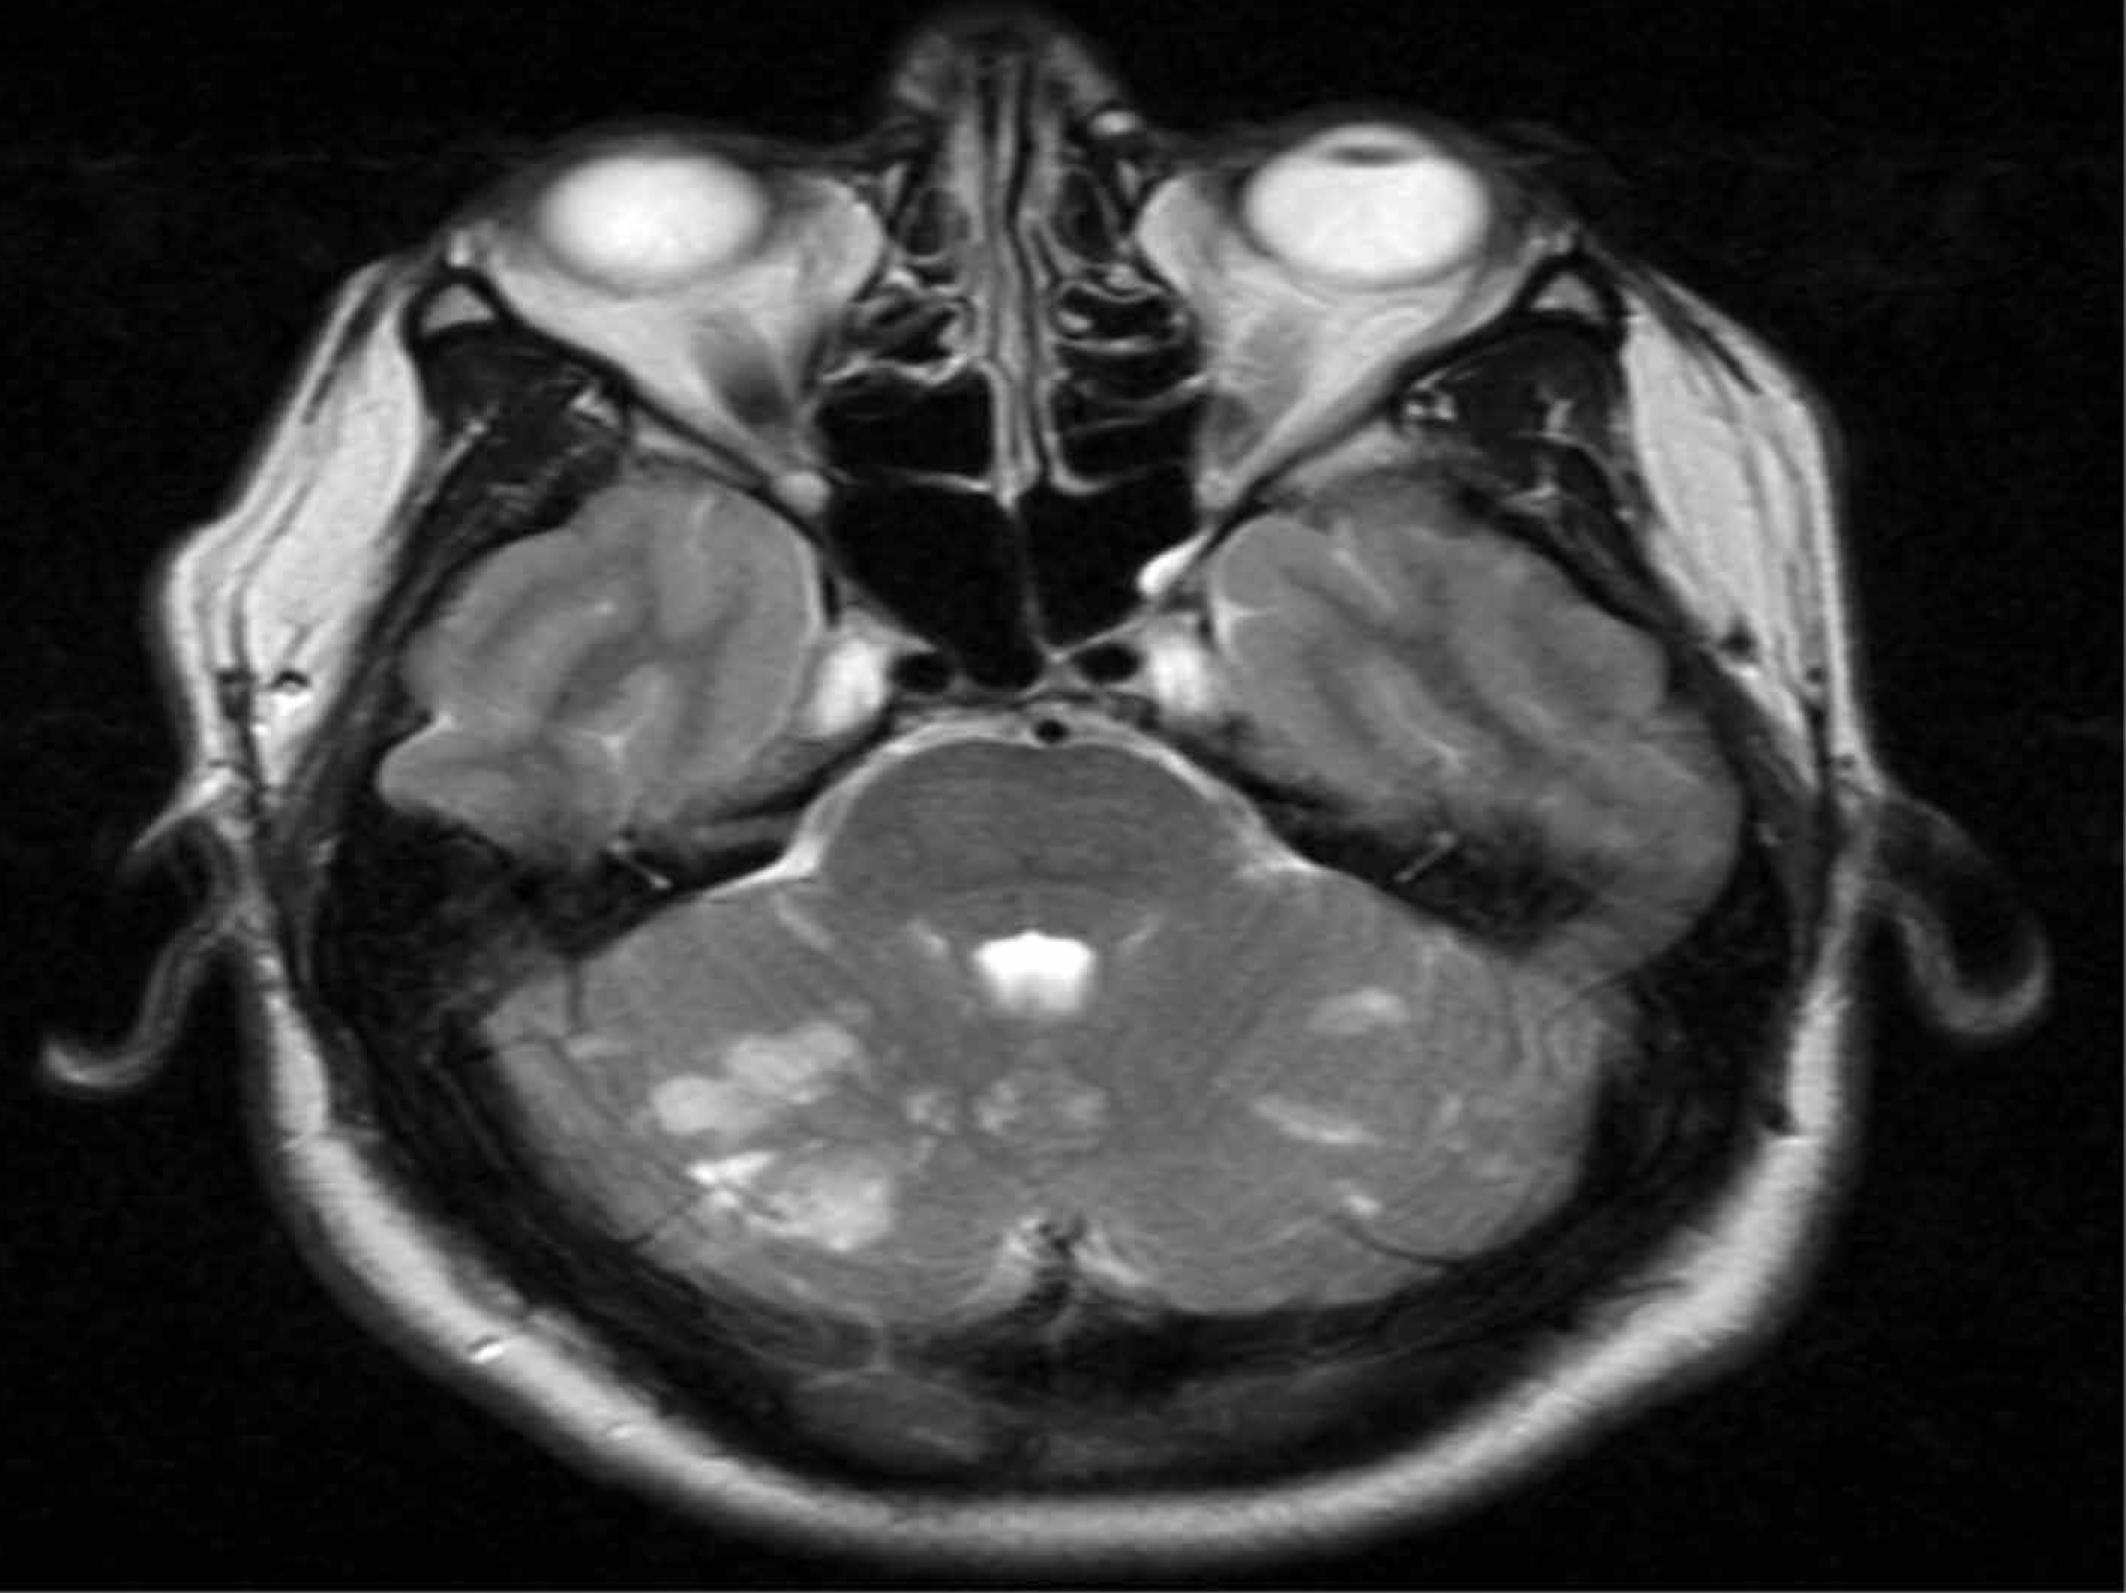

He was admitted to hospital and underwent a CT scan, which found multiple infarcts, cerebellar hemispheres and vermis. An MRI/MRA (see Figure 1) found multiple areas of acute infarction in cerebellum bilaterally and a small area of infarction in the left thalamus and occiput. There was no brainstem infarction and no infarction in any area supplied by the carotids. The MRA found thrombus in the left posterior cerebral artery (fairly distal). No other abnormalities in the intracranial arteries or neck arteries were found.

Figure 1.

MRI showing multiple areas of cerebellar infarctions.